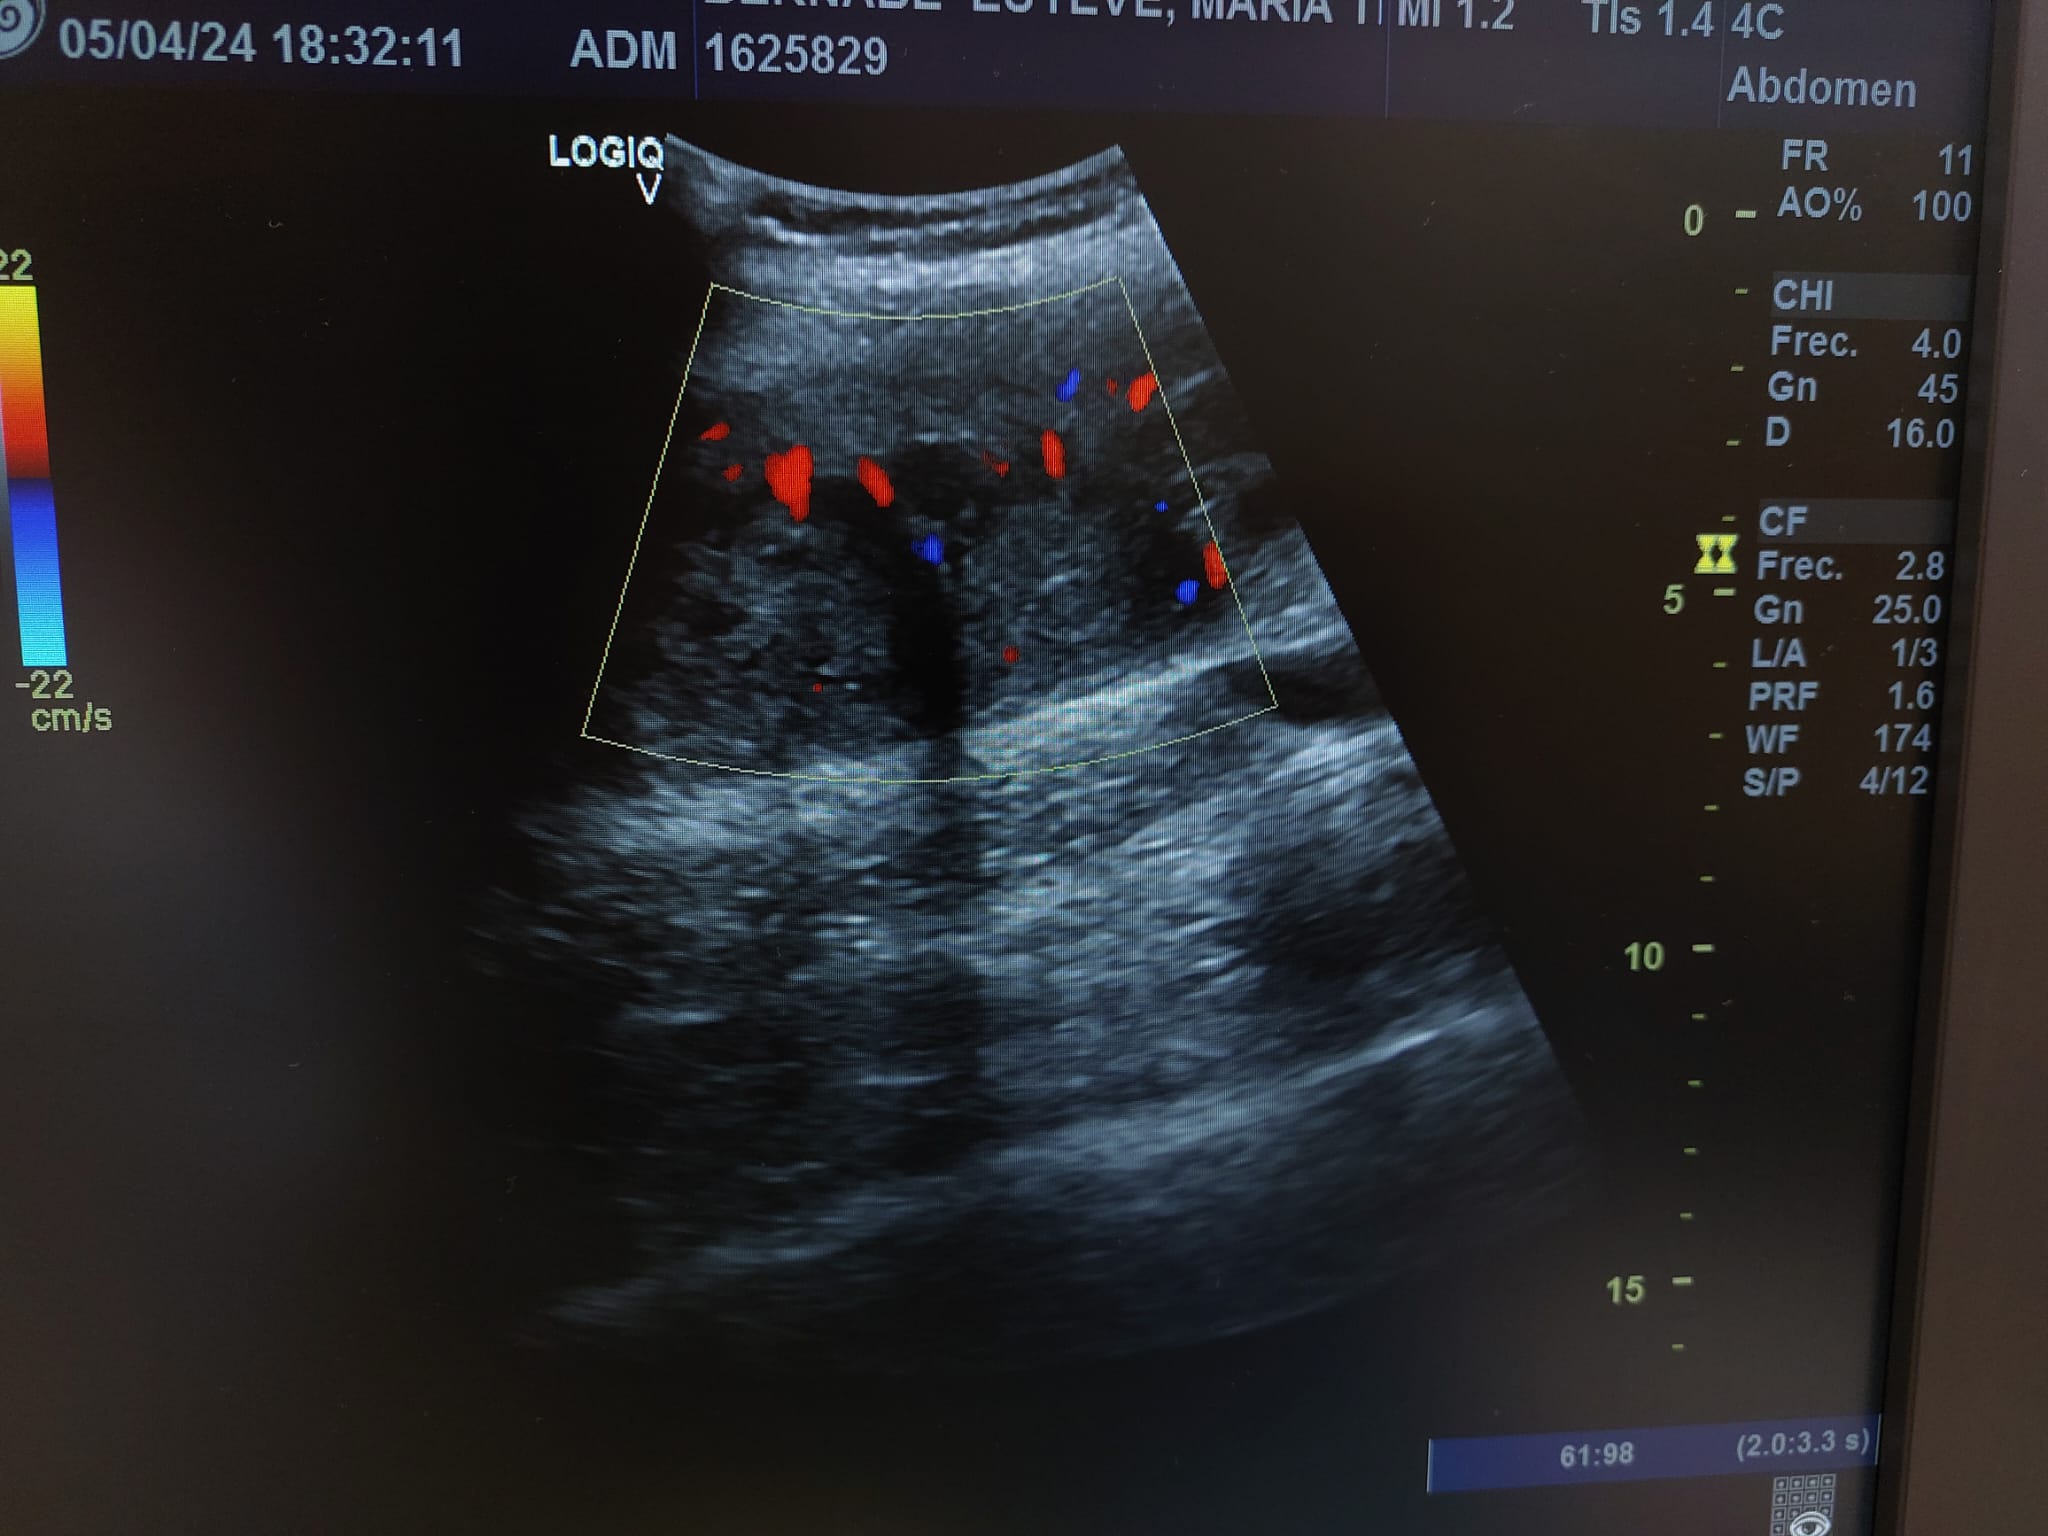

Descripción de los hallazgos ecográficos y las imágenes más relevantes para la resolución del caso

Se realiza ecografía observando colección anecoica a nivel muscular compatible con hematoma organizado, de aproximadamente 7 x 4 cm.

En el seguimiento se observa evolución tórpida sin mejoría clínica y en la ecografía de control se observa aumento notable de tamaño respecto al previo, estructura heterogénea de imagen anecoica con septos internos. Se aprecia edema intramuscular perilesional y captación al activar el Doppler. Se plantea la posibilidad de un hematoma sobreinfectado o, debido a su importante crecimiento, una probable etiología neoplásica. Tras hallazgos descritos en consulta, COT solicita de forma urgente la realización de RNM y biopsia de la lesión. Posteriormente, el resultado de las pruebas complementarias confirman diagnóstico de sarcoma histiocítico.